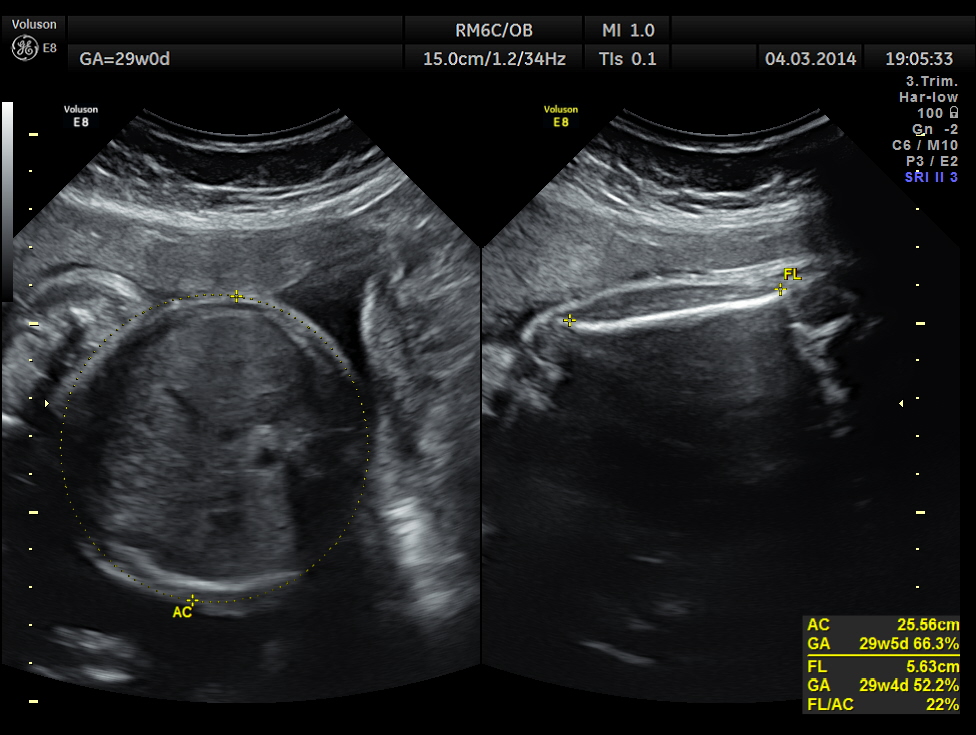

The following images were obtained. Unilateral choroid plexus cyst was seen .

Images of the other organs are given below.